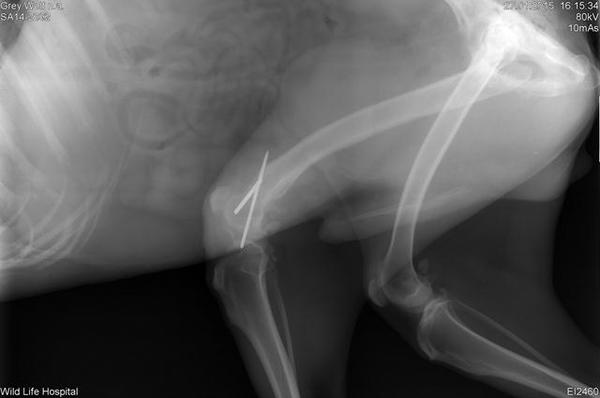

Bacağı kırılan kurt zorlukla yolun kenarına kadar sürüklenmeyi başardı. Bu halde hayatta kalması imkansızdı. Neyse ki onu bir hayvansever farketti ve derhal veterinere götürdü.

Köpeğin ayağının kırıldığı anlaşılınca hemen operasyona alındı.

Operasyon başarılı geçse de iyileşmesi için önünde uzun bir süreç vardı.